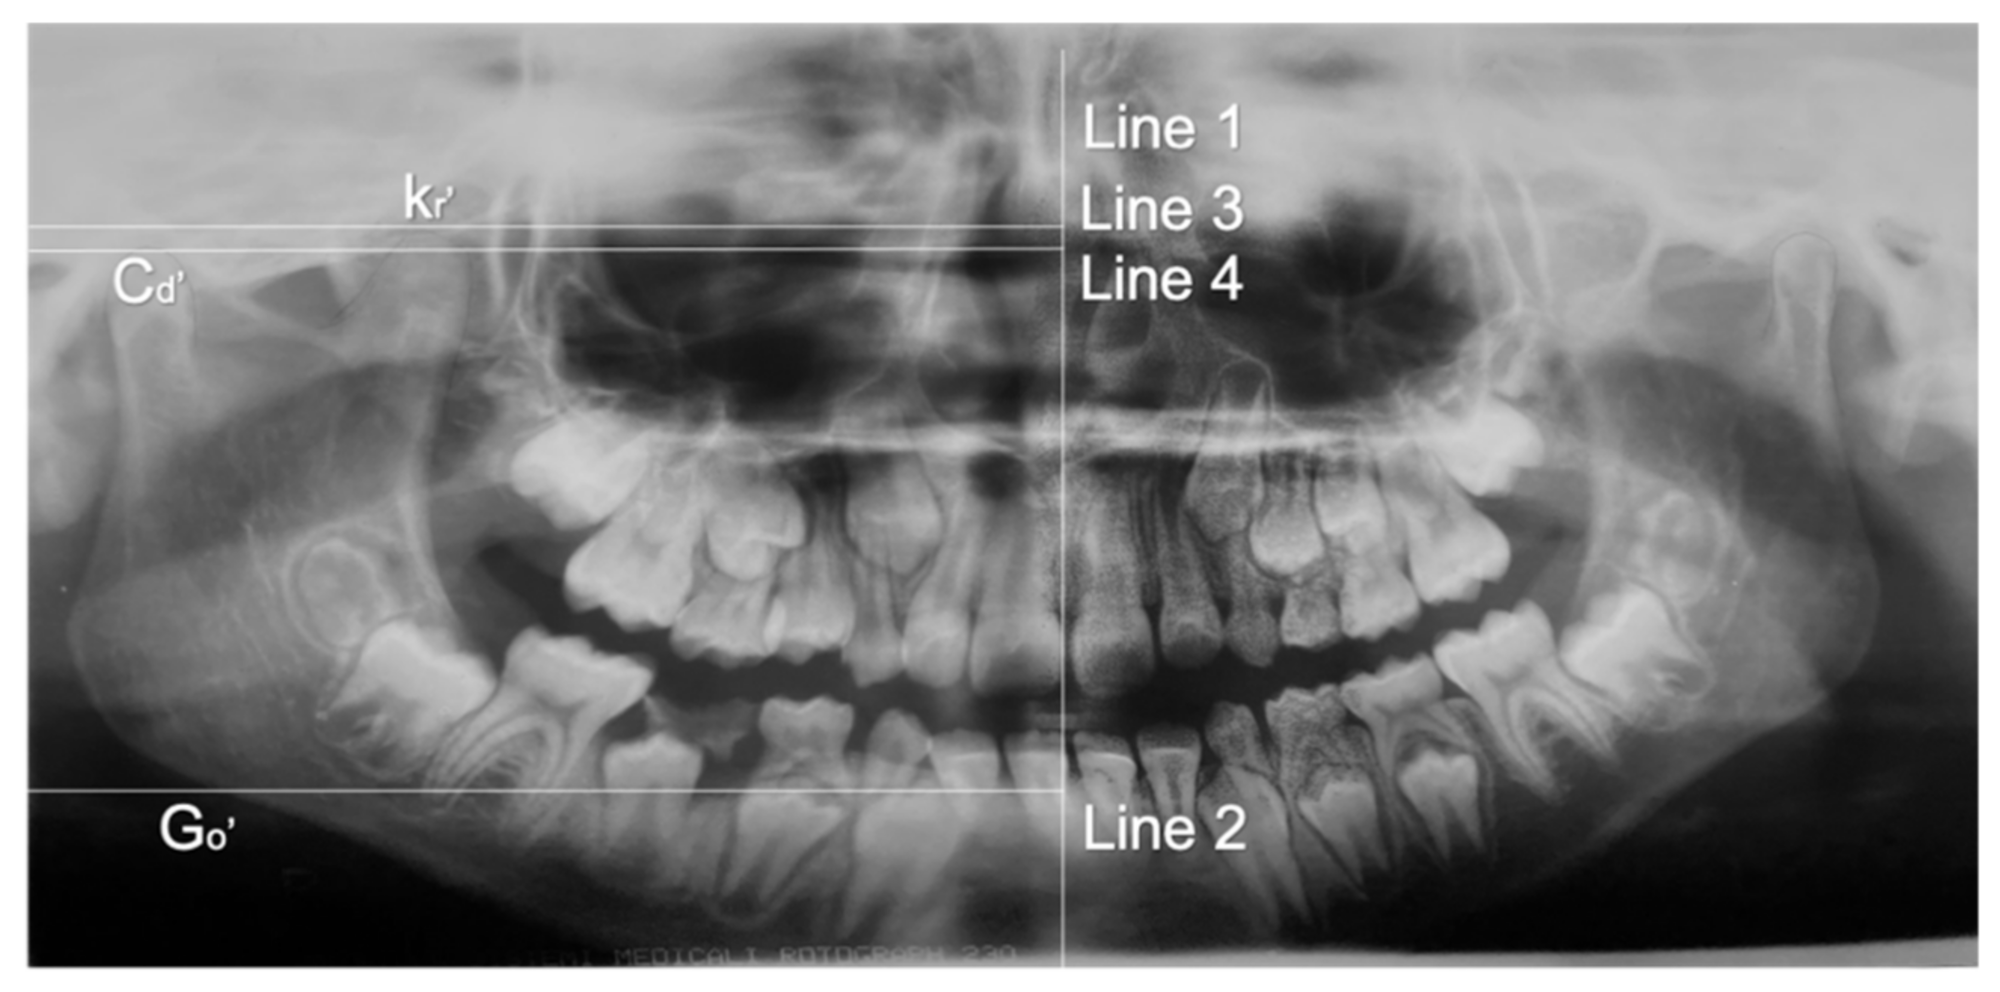

- Kubota, Y.; Takenoshita, Y.; Takamori, K.; Kanamoto, M.; Shirasuna, K. Levandoski panographic analysis in the diagnosis of hyperplasia of the coronoid process. Br. J. Oral Maxillofac. Surg. 1999, 37, 409–411. [Google Scholar] [CrossRef]